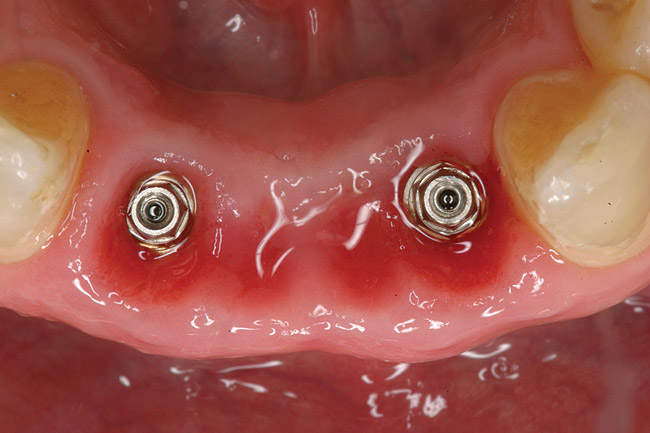

Preoperatively, 1 g of amoxicillin was administered. Using local anesthesia (lidocaine 1:100,000 epinephrine), extractions of teeth No. 23 to No. 26 were performed without raising a flap and with gentle luxation to preserve the remaining facial osseous plate. The sockets were curetted prior to implant placement. A vacuum-formed surgical guide, fabricated based on a diagnostic wax-up of the desired tooth positions for the subsequent fixed prosthesis, was used during implant placement. Osteotomies were performed at sites No. 23 and No. 26 and positioned toward the lingual aspects of the sockets (Figure 3A and Figure 3B). Two tapered implants (OsseoTite™ 313, BIOMET 3i™, Palm Beach Gardens, FL) measuring 3.25 mm x 13 mm were placed. Conical prosthetic abutments (3-mm height) were used to facilitate joining the two implants in a screw-retained fixed partial denture (Figure 4). A laboratory-processed acrylic-resin provisional restoration was altered to allow connection to the temporary cylinders. The provisional was placed into the vacuum-formed surgical guide that was now used to maintain the provisional in the correct 3-dimensional position (Figure 5) while being attached to the temporary cylinders with acrylic resin intraorally. Once a sufficient amount of acrylic resin was placed to secure the cylinders to the provisional, it was removed from the mouth and its contours were completed at the laboratory bench (Figure 6A). The two central incisor sockets were grafted with small-particle allograft material (Puros® Allograft, Zimmer Dental, Carlsbad, CA) to maintain gingival architecture beneath two ovate pontics (Figure 6B). The provisional restoration was inserted and the screws tightened to 20 Nt-cm of torque.

Figure 4  Tapered implants with conical transgingival abutments and temporary cylinders in place.

Figure 4